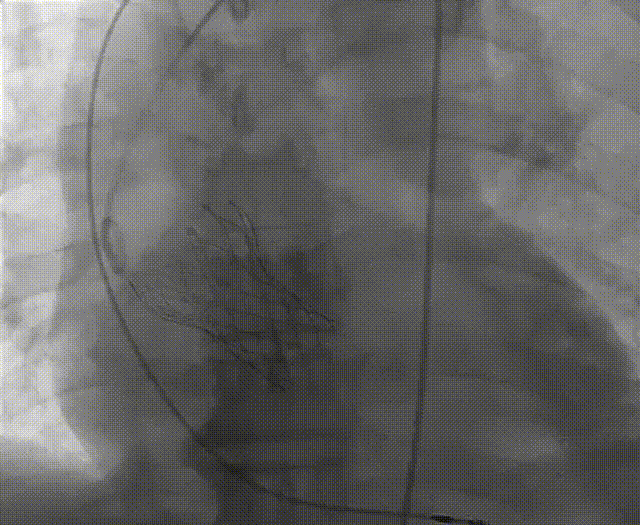

根部造影

左冠脉提前植入延长导管,预埋冠脉导丝。

20mm球囊预扩张,无腰征,无造影剂泄露。

vitaflow tav24瓣膜轻松过弓初始定位瓣环0位开始释放,班第一次释放瓣膜在转移到瓣上,综合决定回收采取第二次瓣膜释放。

第二次精准零位释放,决定完全释放。

释放后多体位观察造影,瓣膜位置良好,展开良好,轻微瓣周漏。